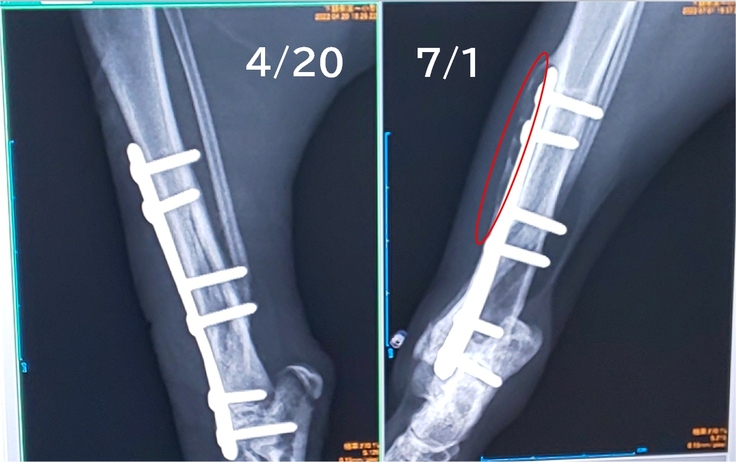

骨の調子は…「若いだけあって回復が早いね」いただきました👏✨

素人目にはよくわかりませんが、骨が太くなっていることだけわかります。

いよいよ、7月7日、プレート除去の予約をして参りました。

6本のボルトで固定している場合、スタンダードなのは1度で外すと穴だらけで再骨折の可能性が出てしまうため、2回に分けて外すそうです。

ただ、ガッツくんは成長期。プレートの上に骨がかぶりかけているため、1度で外した方が良いかもしれないそうです。

【赤丸の箇所:プレートの上に白くモヤっぽいのが再生中の骨らしいです】

1回目の手術の時に、様子を見て決めていただくことになりました。

こればっかりは先生にお任せするしかありません(>_<)